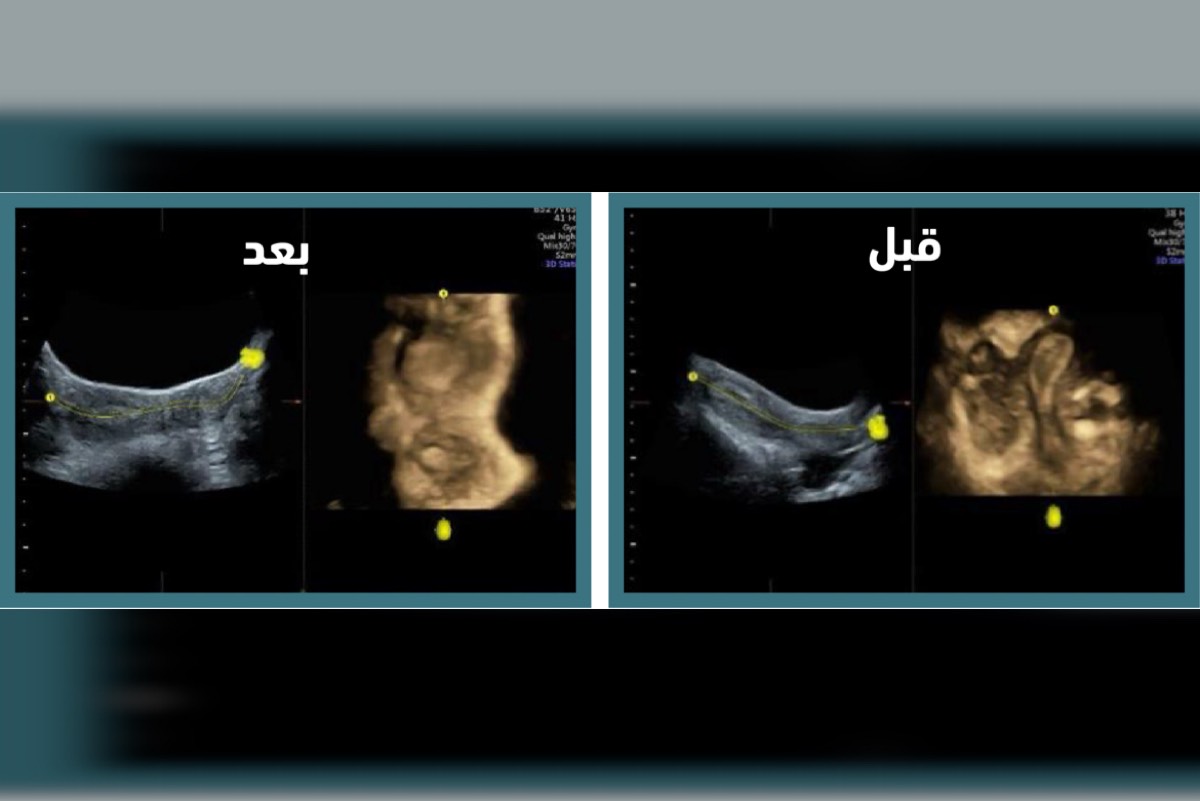

وبعد إجراء الفحوصات الطبية اللازمة، بما في ذلك السونار ثلاثي الأبعاد والرنين المغناطيسي، تمكن الفريق الطبي المتخصص بمستشفى النساء والولادة من تشخيص الحالة بدقة.